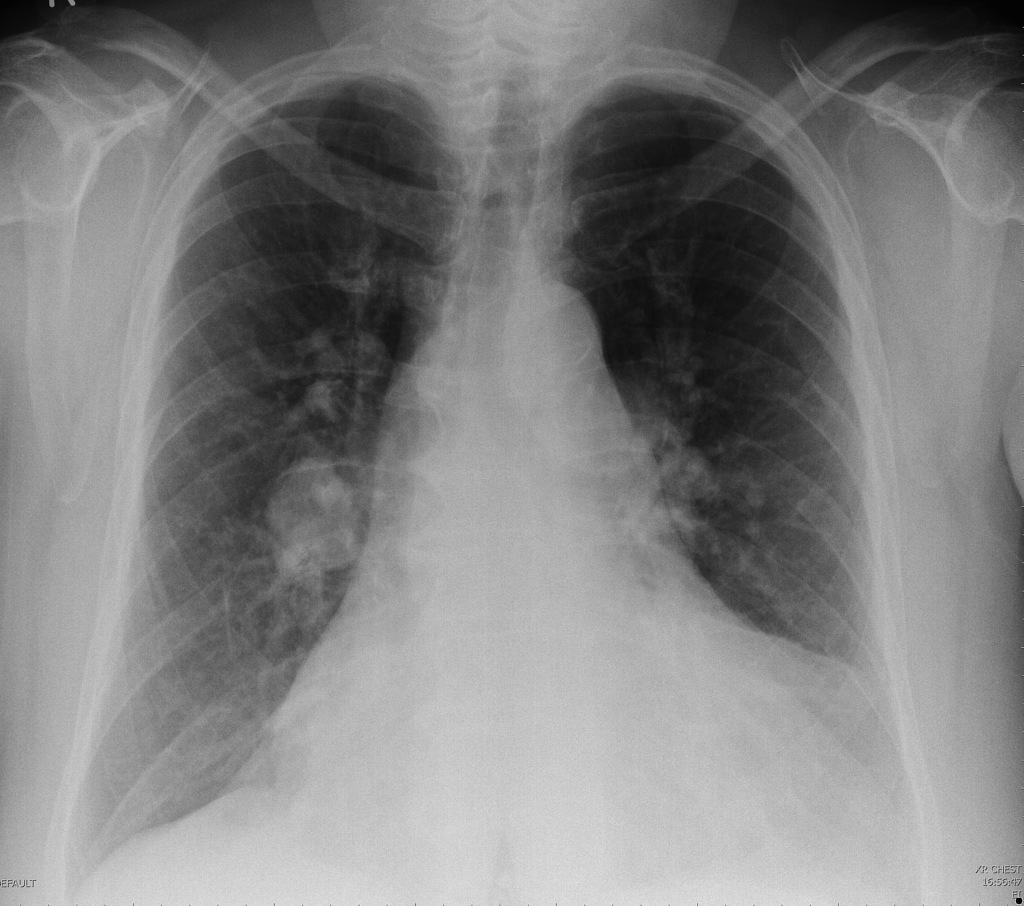

X-Ray Images

Fleischner sign (enlarged pulmonary artery)

- sensitivity: ~14%

- specificity: ~92%

- positive predictive value: ~38%

- negative predictive value: ~76%